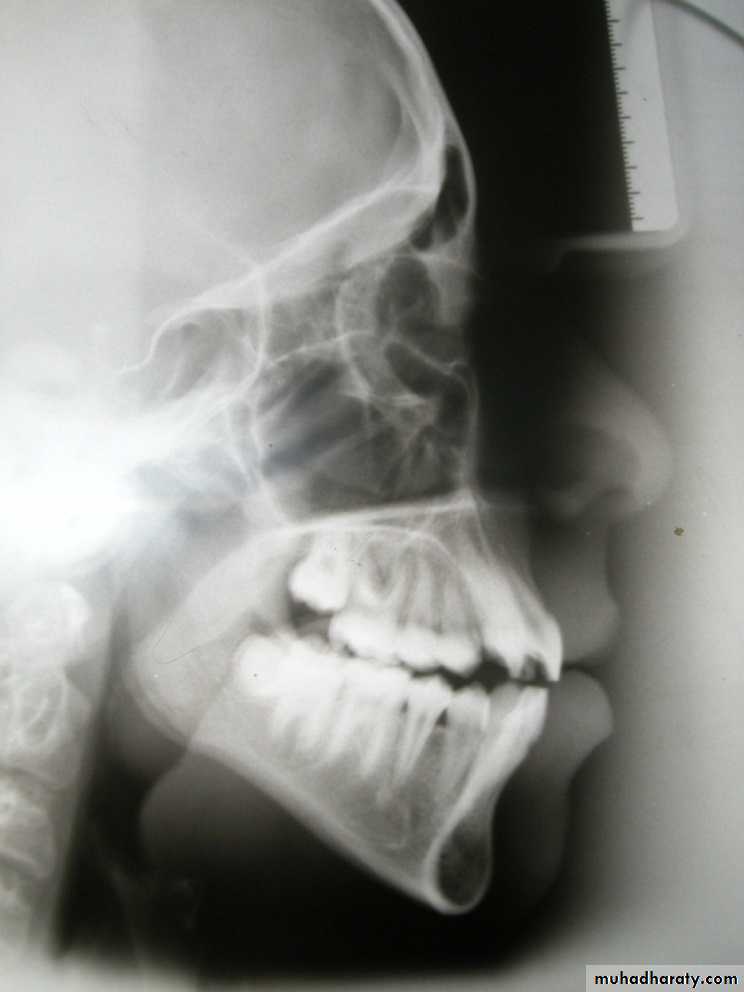

Cephalometric lines of reference

6. Mandibular plane:

Me - Go

7. Occlusal plane:

Cusp tips of molars – tip of lower incisor

8. Functional occlusal plane (FOP):

Cusp tip of lower 1st molar –

cusp tip of lower 1st premolar

9. The facial plane:

N - Pog

10. Line from point A to pogonion:

A - Pog